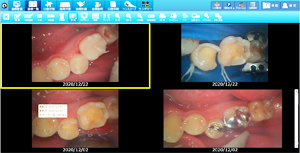

• ラバーダムを使用した治療画像